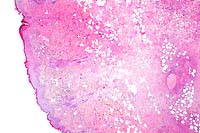

2x

obj

40x

- Case 24-3. Haired skin. The dermis and subcutis beneath

a thickened epidermis is expanded by edema and infiltrating inflammatory

cells which surround and separate normal dermal elements. High

power of the epidermis illustrates multiple brightly eosinophilic

intracytoplasmic inclusions within keratinocytes, multifocal

neutrophilci infiltrates, and parakeratotic hyperkeratosis.